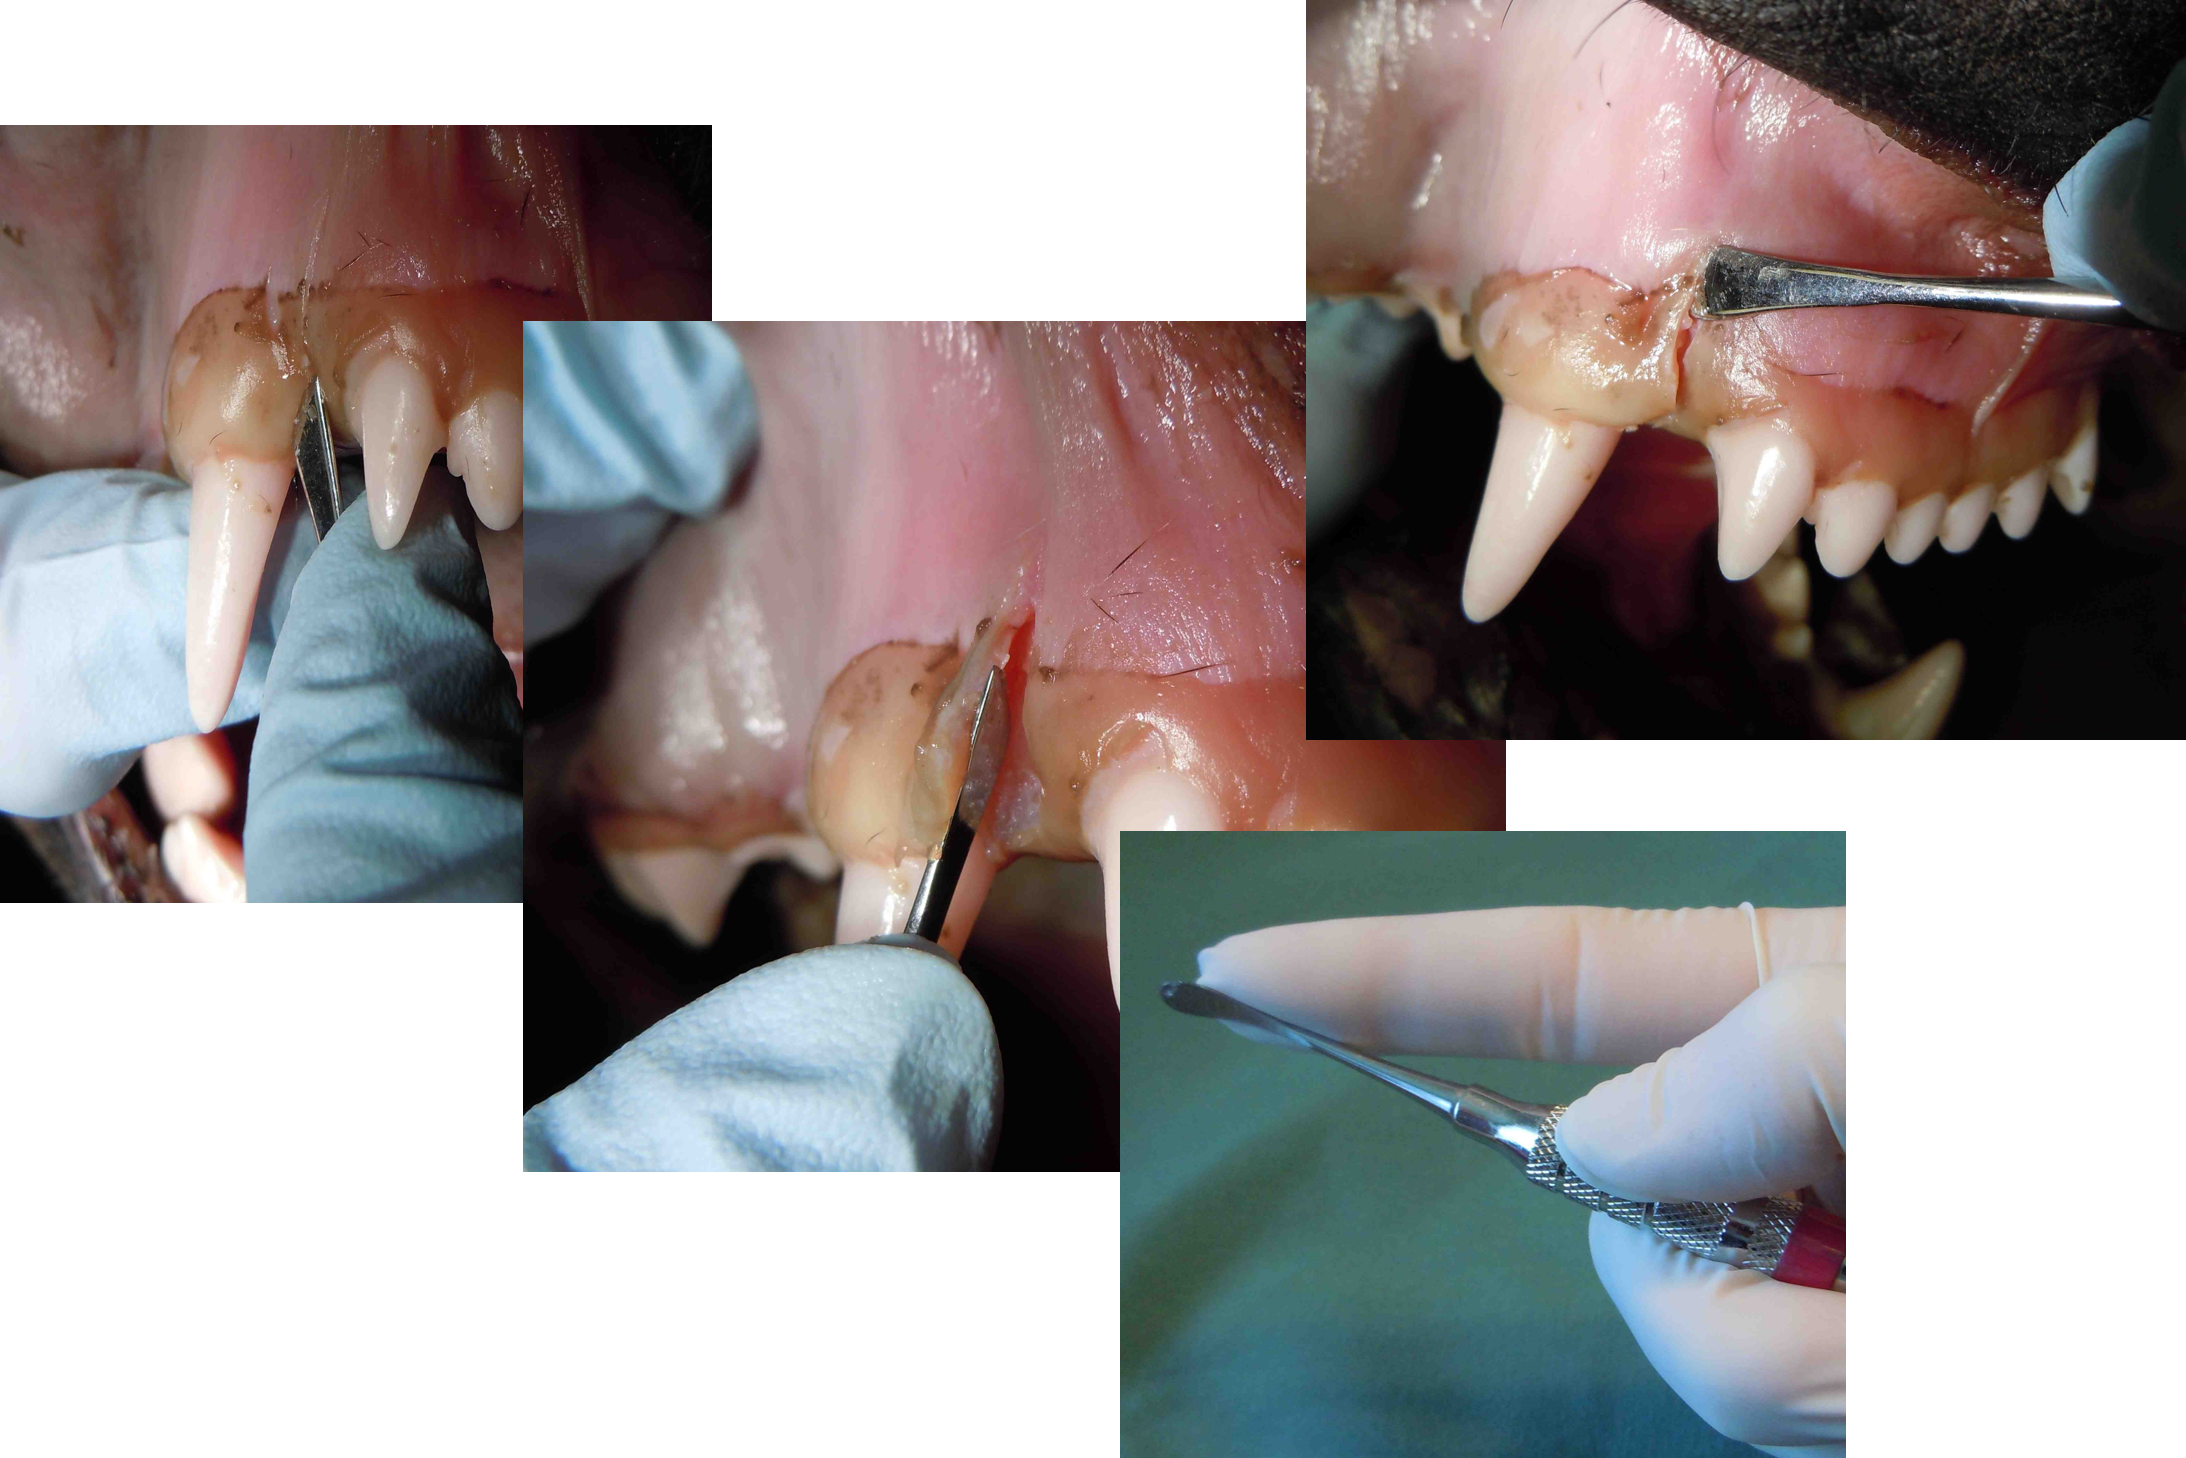

Exodontia

Extractions

Techniques for gingival flaps, bone removal, sectioning teeth, removing teeth, suturing flaps.

Hands on Skill Development

Practical training sessions often focus on extraction techniques and other procedures that require confidence and precision. To allow participants to learn safely, these sessions use non-living specimens that provide realistic practice without patient risk. Hospitals are responsible for sourcing suitable specimens; guidance can be provided if needed.